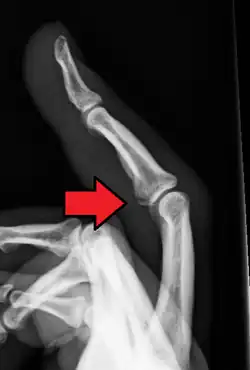

Avulsion fracture of the proximal middle phalanx on the palm side | |